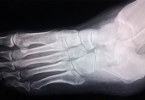

脚大拇趾关节处有个小骨头凸起是什么原因

脚大拇趾关节处的小骨头凸起可能是拇外翻或痛风石,通常与遗传、穿鞋不当、关节炎等因素有关。建议及时就医明确诊断。1、拇外翻拇外翻是足部常见畸形,表现为大拇趾向外偏斜,第一跖骨头内侧形成骨性凸起。长期穿窄 ...